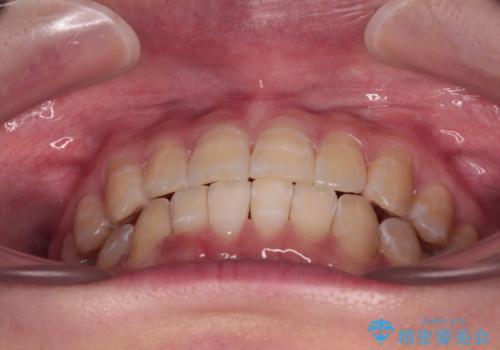

下顎前歯のデコボコが集中しており、奥歯の咬み合わせは、上顎に対して下顎が前方位にある状態でした。下顎の歯列を後方へ移動させる治療はインビザラインの得意とするところですので、1年程度で無事に治療を終えることができました。

【モニター】下顎前歯のデコボコをインビザラインできれいに